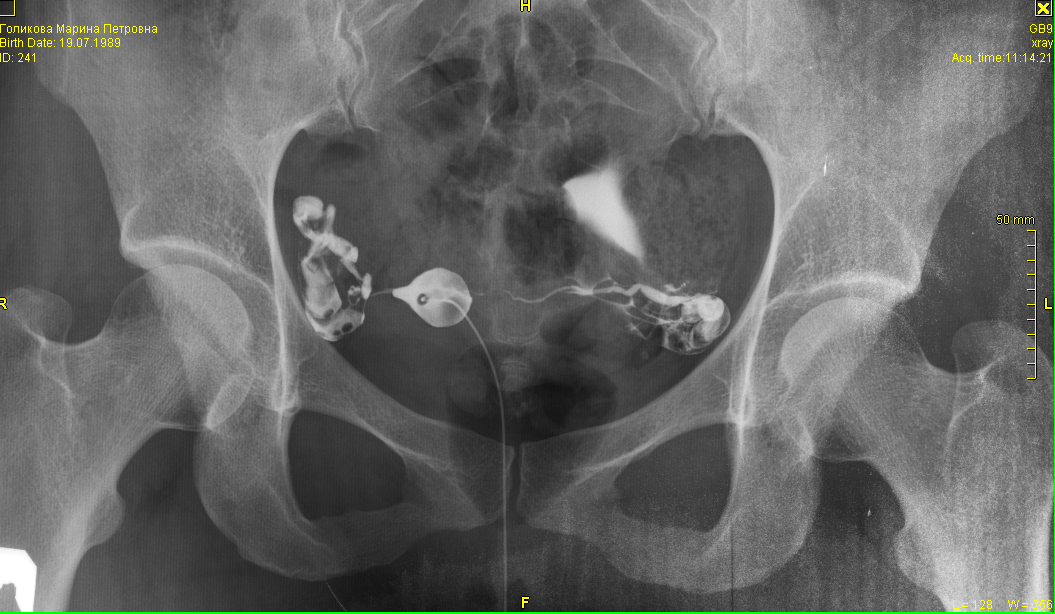

Медицинские снимки: Проходимость маточных труб

Раздел: Кадры-подсказки